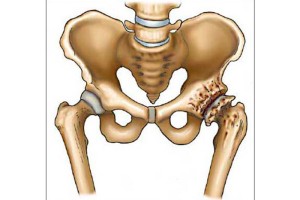

Артроз тазобедренных суставов относится к дистрофическим заболеваниям. В его основе лежат дегенеративные изменения хрящевой и костной ткани сустава, вследствие чего возникают болевые ощущения и нарушается функция движения. Это изношенность сустава — естественный процесс старения. Но ряд факторов могут ускорить этот процесс:

- При 2-й степени коксартроза в процесс вовлекаются костные структуры, возникают костные разрастания, деформация головки бедренной кости, начинают формироваться кисты. Боль при ходьбе становится значительной, человек начинает щадить больную ногу при ходьбе, тем самым нагружая здоровую.

- При 3-ей степени коксартроза преобладают разрастания костной ткани, формируются образования, которые вызывают болевые ощущения и в покое. На этой стадии также возникают переломы, так как костная ткань сустава перестает быть состоятельной.